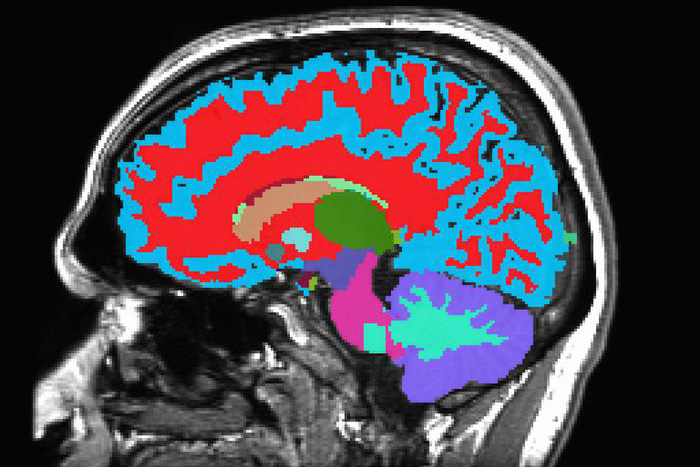

Biologically speaking, some people age faster than others. Your aging rate can affect your health and disease risks. If you knew this rate, you might be able to work with your doctor to slow the aging process. A research team developed a way to measure aging based on a single brain scan.

Most of the study participants also had an MRI scan at age 45. In the new study, the team combined the Pace of Aging scores with the MRI scan data. They developed a new aging measurement, called Dunedin-PACNI, based on the brain scans alone. They then tested the new tool with data collected on thousands of people from other studies.

DunedinPACNI accurately predicted how quickly a person’s ability to think and remember weakened with age. It also could predict a person’s risk of future disease and death.